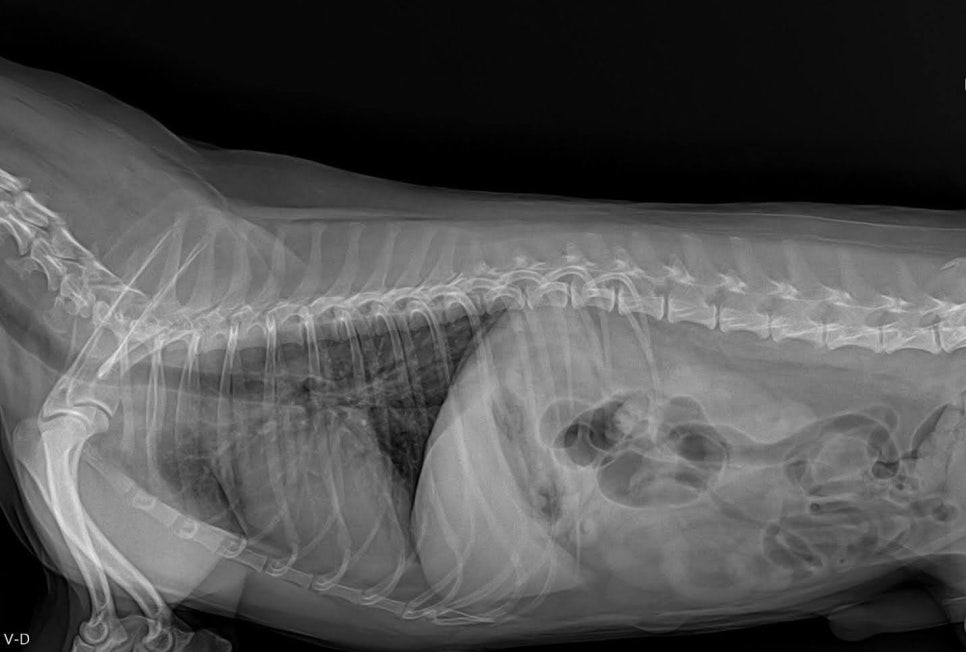

마취 전 혈액검사 및 방사선 검사를 통해 전신 상태와 수술 적합 여부를 확인했고 특이 이상 없이 안정적인 상태로 확인되었습니다.

수술 전 흉부방사선 검사 / 출처: 라온동물메디컬센터